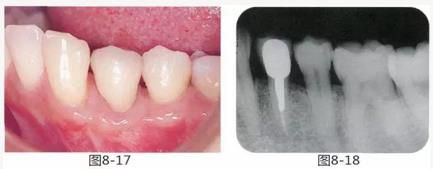

圖8-17 最終佩戴修復(fù)體時的狀態(tài)。完成修復(fù),對鄰牙的牙周組織幾乎無影響。

圖8-18 佩戴修復(fù)體時的X光照片。